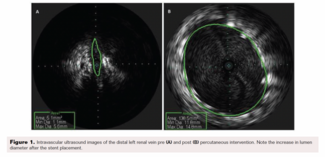

A case of 34-year-old woman with pelvic congestion syndrome with nutcracker syndrome that was successfully treated.